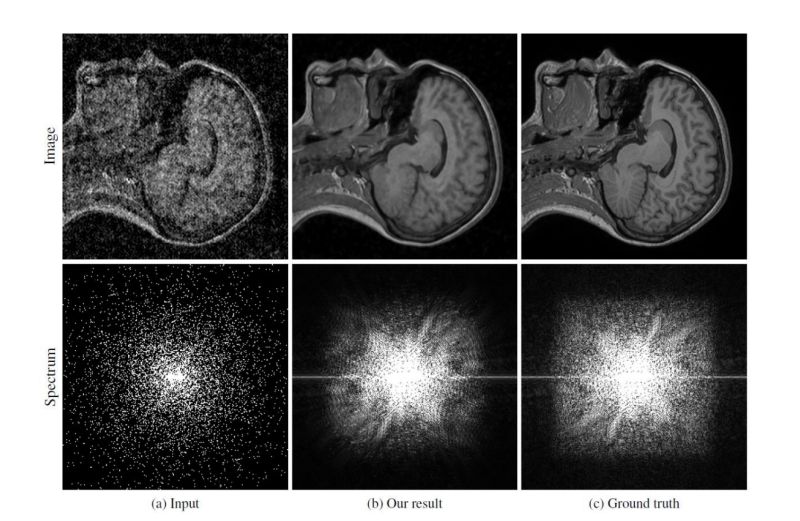

从左到右:输入的噪声图像、去噪图像、和原始图像

来自IXI数据集的50名人类受试者的近5000张图像被用于训练Noise2Noise的MRI图像去噪能力。在没有人工噪声的情况下,结果可能比原始图像稍微模糊一些,但仍然很好地还原了清晰度。

MRI图像去噪